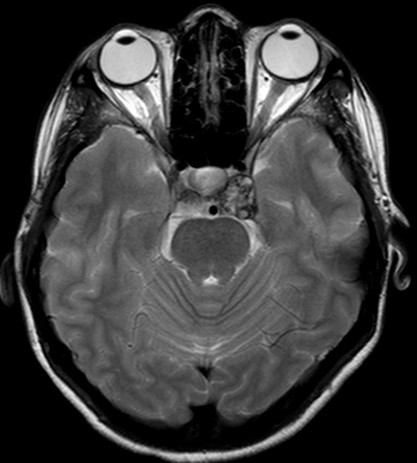

A hemangioma is a benign vascular tumor of the brain, which rarely occurs in the cavernous sinus. We report a rare case of cavernous sinus hemangioma presenting with binocular diplopia. A 23-year-old lady presented with binocular diplopia associated with restricted left lateral gaze for 3 months. Visual acuity of both eyes was 6/6 with normal pupillary reaction. Both anterior and posterior segment were unremarkable. Contrasted computed tomography of brain showed an irregular mass within the left cavernous sinus causing pressure effect on the adjacent bone. Cerebral magnetic resonance imaging (MRI) showed a convexity in the left cavernous sinus, with a well-defined heterogeneous lesion with mixed hypo and hyperintensity in T1WI and T2WI; post gadolinium contrast, it was minimally enhanced. The patient was managed conservatively and at one-year post presentation, her symptoms improved but the lesion morphology and size remained static. We highlight the classic radiological presentation of a hemangioma and discuss the features differentiating it from the more commonly observed meningioma seen in the cavernous sinus.References